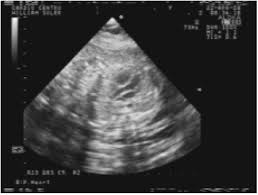

El diagnóstico por imágenes en la enfermedad cardiovascular ha evolucionado de modo exponencial en las últimas décadas. Más allá de la reconocida utilidad de la angiografía y de los crecientes avances en la tomografía computarizada multicorte, la ecocardiografía es sin dudas el principal recurso diagnóstico para los especialistas en Cardiología.

En los primeros semestres, se revisan conceptos anatómicos y relacionados con la biofísica de las imágenes, para avanzar en las etapas posteriores hacia los recursos que ofrece la ecocardiografía bidimensional, la técnica Doppler y los sorprendentes métodos intraesofágicos e intravasculares.